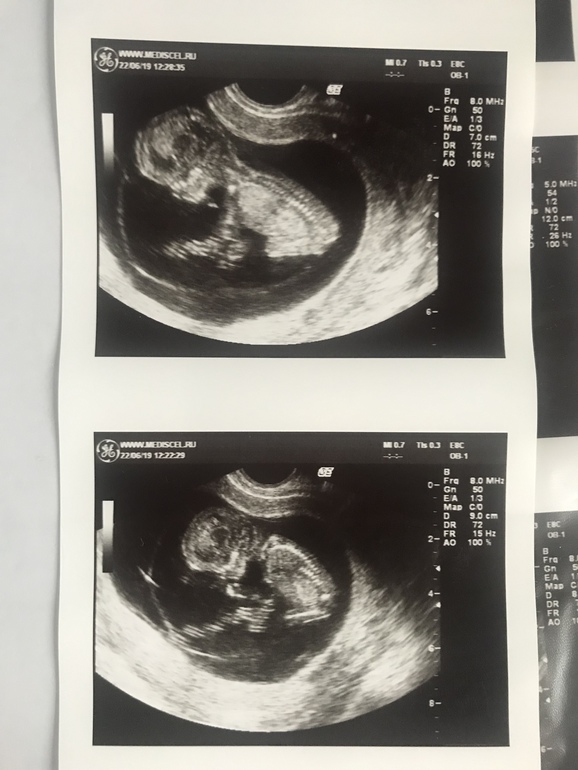

На сроке 12 недель я решила поехать к моему предыдущему узисту в Москву, там классное оборудование, хотела показать малыша мужу и дочке) так сказать совместный просмотр. Все было здорово, кроме ТВП 3,2.

Он очень долго меня смотрел, минут 40... но всегда все объяснял, рассказывал, в прочем как и всегда... поэтому я к нему поперлась в такую даль))

Наблюдаюсь я в частной клинике , но по сравнению с Москвой в МО все равно не тот сервис, оборудование или специалисты... один раз за все время УЗИ на скрининге показали малыша, я все ждала страшных слов. Но их не последовало, тут я решила рассказать о предыдущем УЗИ, на что врач удивленно спросила:

« А как же он вас к генетику не отправил, вам нужно к генетику если было такое ТВП, но может он неправильно вам измерил» ( в чем я очень очень сомневалась, ведь это замечательный специалист вел первую беременность и я знаю как многие его уважают и любят)

Через три дня приходят результаты скрининга: кровь отличная, узи тоже.